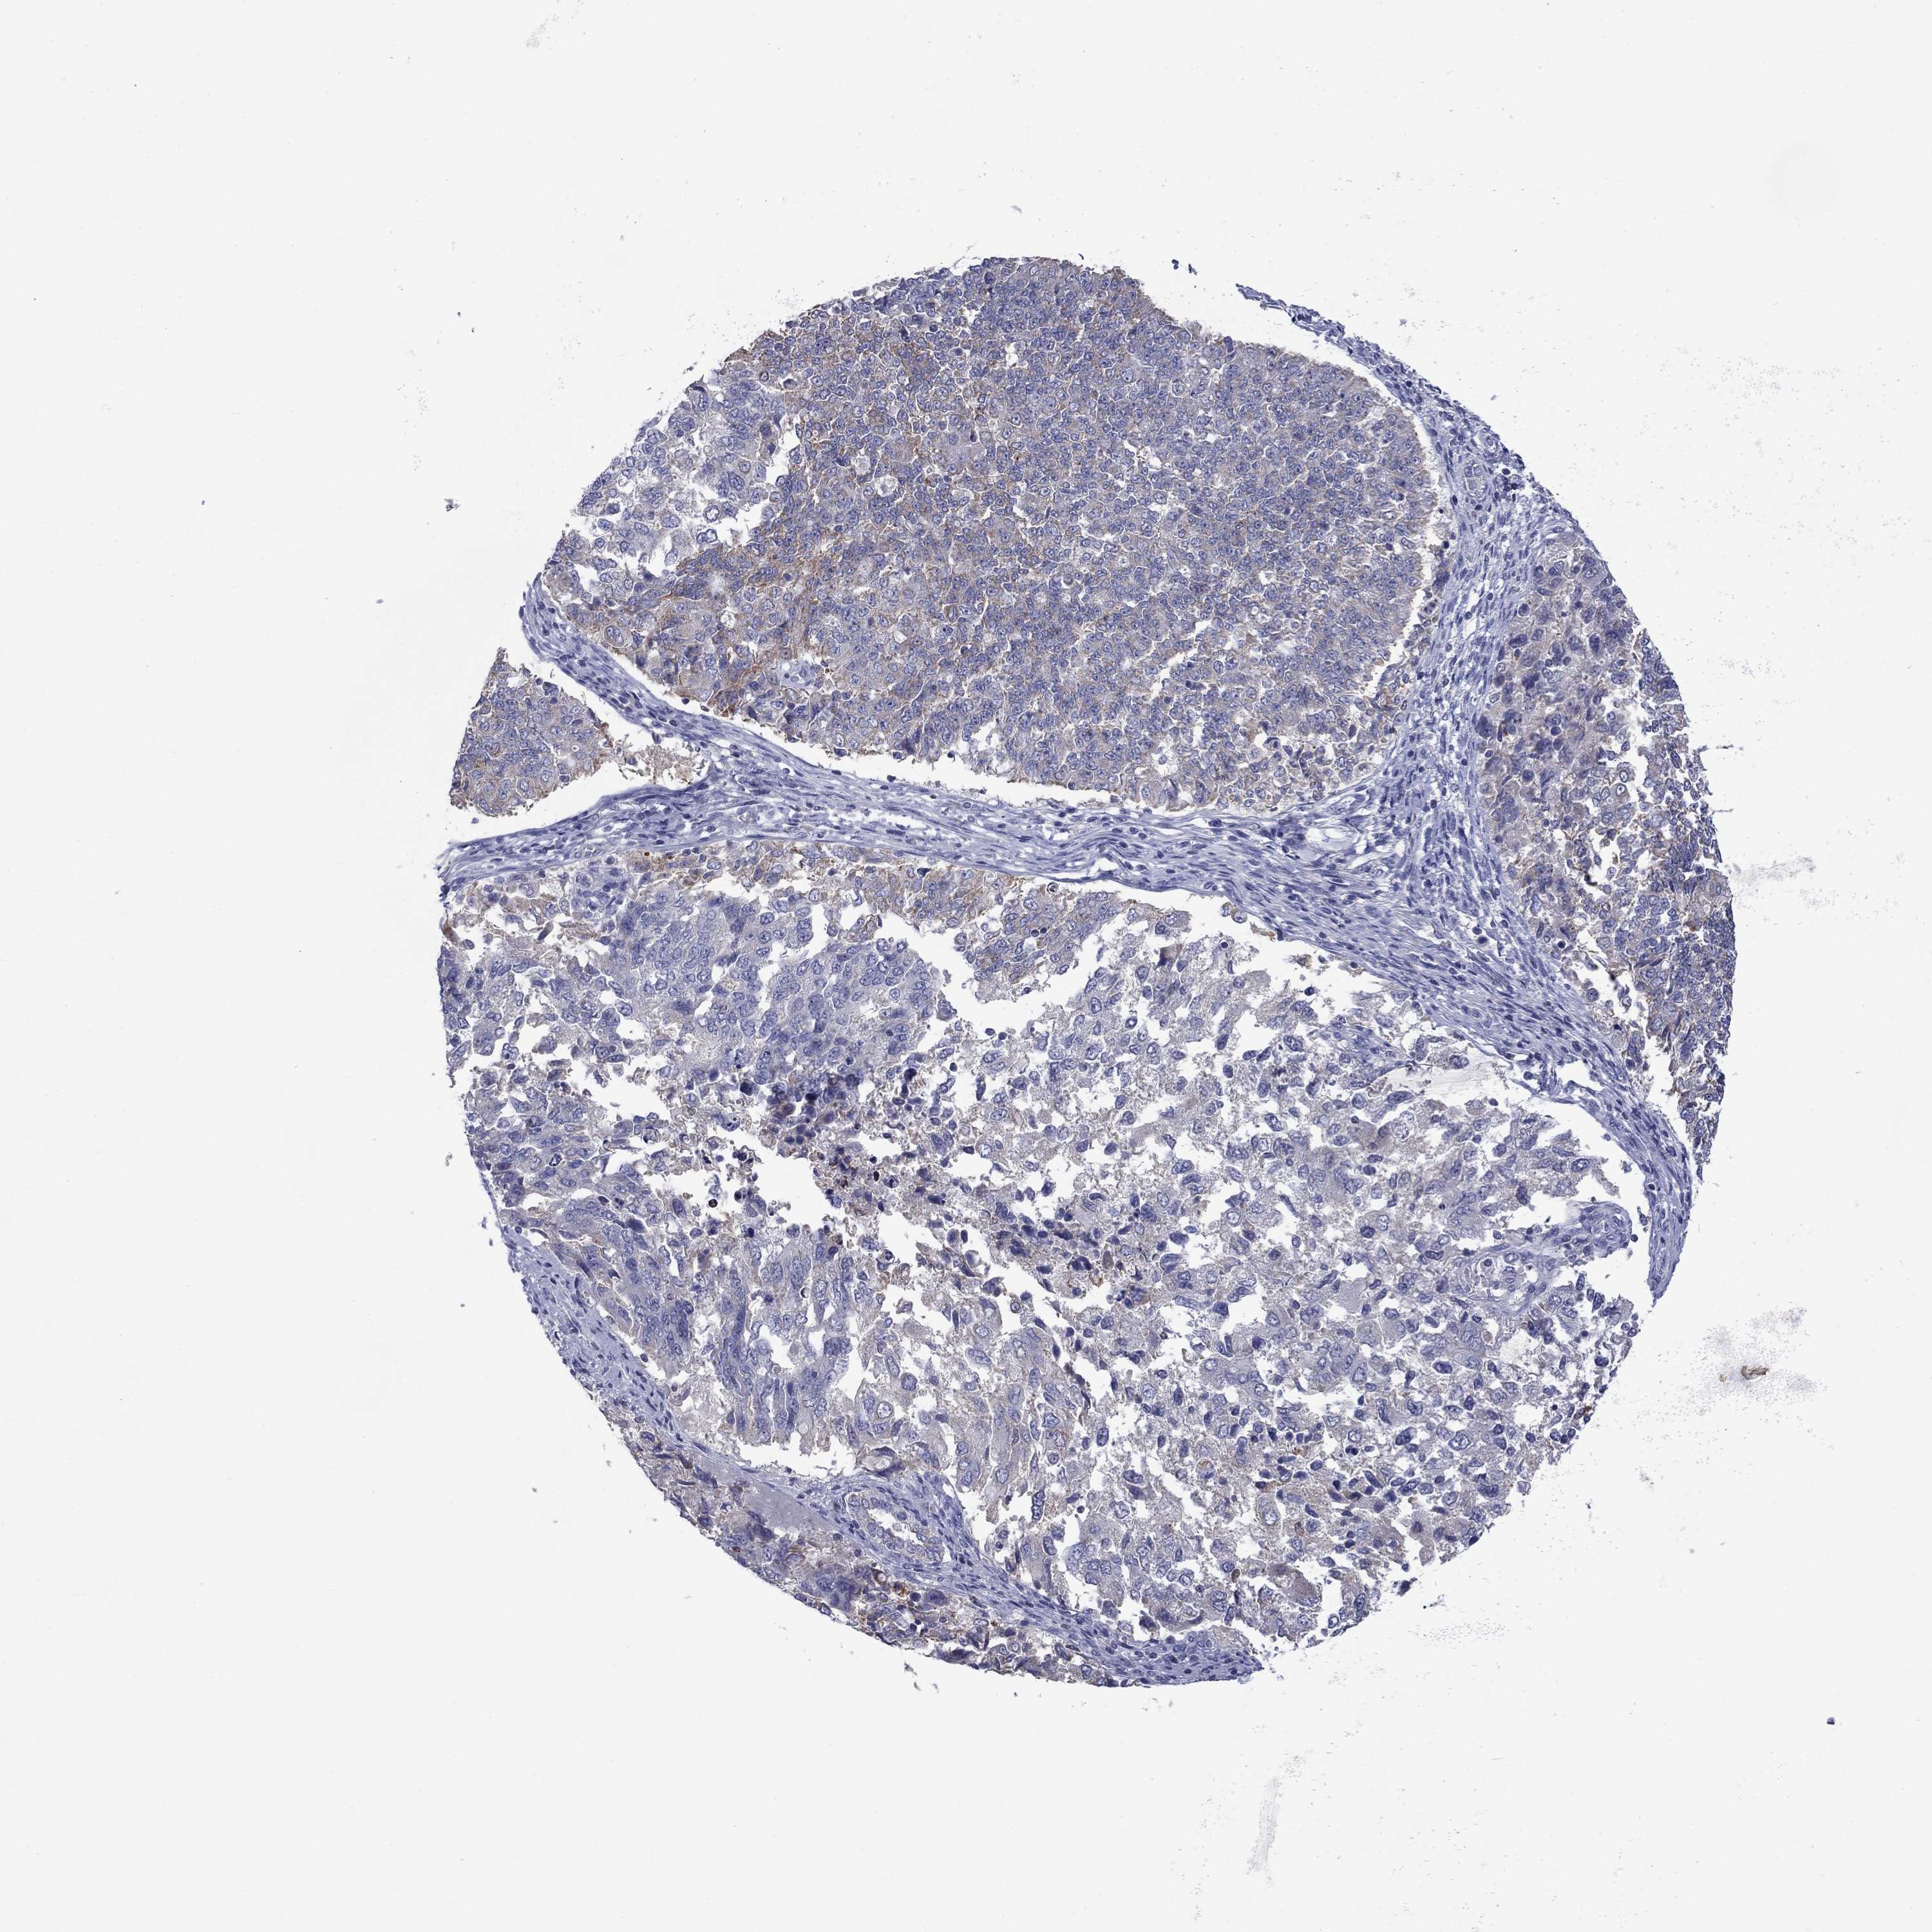

ENDOMETRIAL CANCER - Protein expressioni

A mouse-over function shows sample information and annotation data. Click on an image to view it in a full screen mode. Samples can be filtered based on level of antibody staining by selecting one or several of the following categories: high, medium, low and not detected. The assay and annotation is described here.

Note that samples used for immunohistochemistry by the Human Protein Atlas do not correspond to samples in the TCGA dataset.

Antibody stainingi

Antibody staining in the annotated cell types in the current human tissue is reported as not detected, low, medium, or high, based on conventional immunohistochemistry profiling in selected tissues. This score is based on the combination of the staining intensity and fraction of stained cells.

Each image is clickable and will lead to virtual microscopy that enables deeper exploration of all samples and also displays staining intensity scores, fraction scores and subcellular localization as well as patient and tissue information for each sample.

Antibody HPA072590

Antibody CAB025217

Staining

High

Medium

Low

Not detected

Intensity

Strong

Moderate

Weak

Negative

Quantity

>75%

75%-25%

<25%

None

Location

Nuclear

Cytoplasmic/membranous

Cytoplasmic/membranous,nuclear

Adenocarcinoma, metastatic, NOS